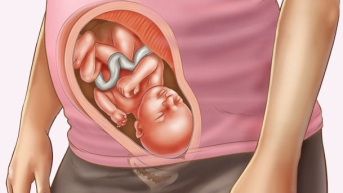

27 semanas

Na 27ª semana iniciamos o 7o mês de gestação e o espaço no útero está cada vez mais apertado para os movimentos do bebê. Ele já consegue abrir e fechar os olhos naturalmente2 e se achar estranho a tranquilidade de algumas horas, não se preocupe, é sinal de que está dormindo. Evite tomar cafeína e alimentos com muito sódio, pois além de atrapalharem o sono e o descanso causam ainda mais inchaços.

28 semanas

Quando chegamos na 28ª semana o bebê começa a ficar ainda mais gordinho, devido à camada de gordura que ele adquire nessa fase. Outro passo importante desse período ao avançar dos 7 meses de gestação é que as retinas se aprimoram, treinando para enxergar o lado de fora. Já a mamãe, está em sua melhor fase e devido aos hormônios sua pele e cabelos nunca estiveram tão bonitos, aproveite! Quando perguntarem: "28 semanas são quantos meses?". Responda que está se aproximando o final dos 7 meses de gravidez.

29 semanas

Já na 29ª semana, o bebê começa a ensaiar para virar e finalmente encaixar. Não se assuste caso sinta um movimento brusco, é sinal que ele já conseguiu achar a posição de nascimento, conhecida como vértex, ficando de cabeça para baixo3. Nesses dias, o cérebro começa a comandar outras tarefas corpóreas como o ritmo da respiração, ficando mais parecida com a forma que será aqui fora.

30 semanas

Completamos os 7 meses de gestação no final da 30ª semana. Agora, o bebê apresenta muita sensibilidade nos olhos, conseguindo distinguir cada vez melhor a claridade do escuro e até mesmo acompanhar luzes do lado de fora da barriga. Nessa etapa, ele responde a estímulos de voz e toque, podendo mover-se caso converse com ele ou acaricie a barriga.

Como está o bebê com 7 meses de gestação?

Com 7 meses de gestação o bebê está exatamente como irá nascer, mas ainda vai ganhar peso até o dia do parto. Ele já tem todos seus órgãos formados e por isso se nascer nessa fase não corre grandes riscos.

Qual o peso do bebe com 7 meses de gestação?

Nesta fase ele pesa em torno de 2 quilos, mas é algo que pode variar para mais ou menos dependendo do bebê. Lembrando que cada bebê se desenvolve no seu tempo e da sua maneira.

Qual a posição do bebê com 7 meses de gestação?

Nessa fase, alguns bebês já podem estar encaixados, outros ainda sentados ou até mesmo atravessados. Ainda que o espaço esteja cada vez mais limitado ele vai conseguir virar para o dia do parto, fique tranquila.